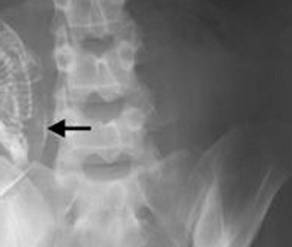

Immaginatevi la sorpresa una volta ritirato il referto delle lastre, quando il medico dice alla donna ‘complimenti, lei è incinta’. In realtà il feto, ormai calcificato nel corpo della donna, era li da ben 40 anni. Una gravidanza di cui evidentemente la donna a suo tempo non era a conoscenza, la morte inaspettata del feto e l’impossibilità del suo fisico dell’espulsione di quest’ultimo a causa della sua grandezza erano le cause dei continui disturbi dell’ignara signora. Un’operazione ha finalmente permesso di dare alla ‘luce’ questo feto di ben 40anni di età. Da non credere!